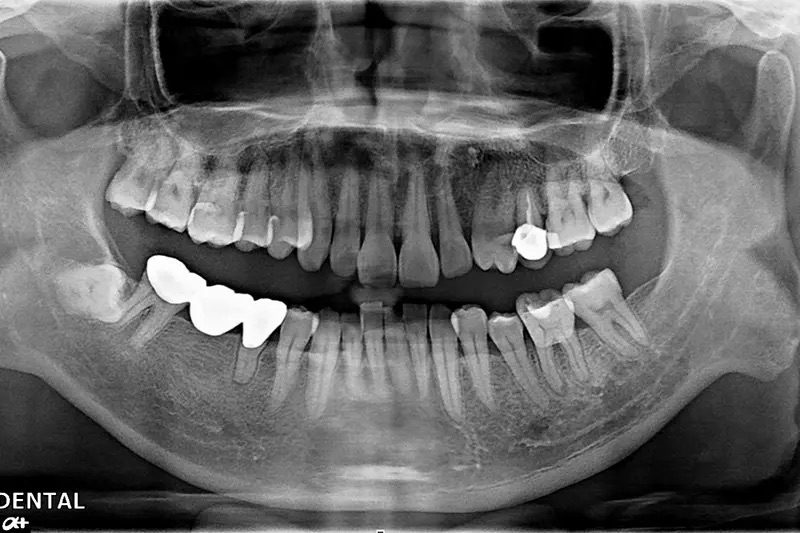

植牙成功案例